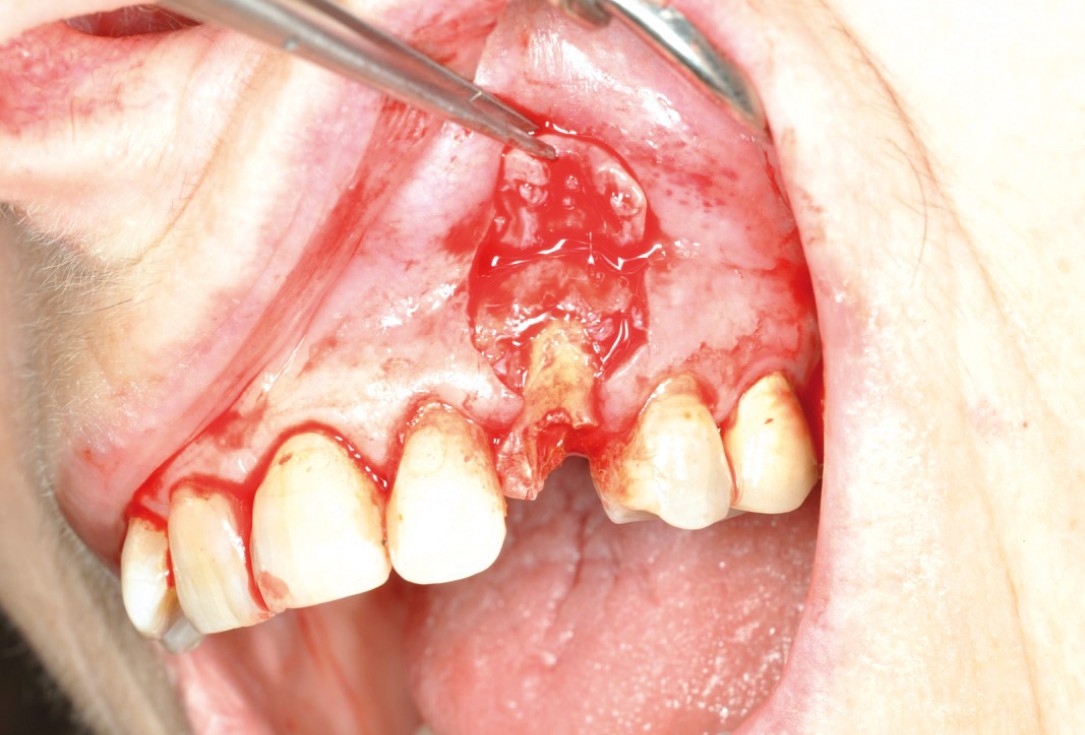

GBR and soft tissue augmentation with cerabone® and mucoderm® - H. Maghaireh & V. Ivancheva

Initial situation: missing teeth #11 & 12 and badly broken #21 root